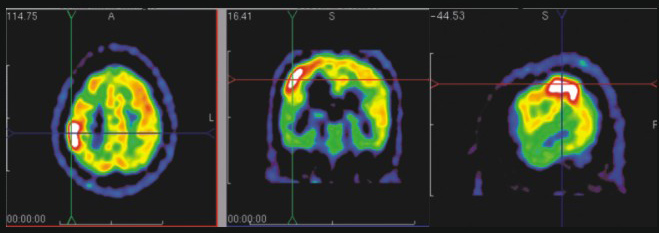

PET-CT可以完成對癲癇患者的術(shù)前定位,文獻(xiàn)顯示:在PET-CT定位指導(dǎo)下進(jìn)行癲癇灶切除術(shù)。93%患者術(shù)后病情可得到控制;PET-CT還可應(yīng)用于Alzheimier`s病(早老性癡呆)診斷、精神疾病的評估;吸毒成癮性評估或戒毒療效診斷;腦外傷后腦代謝狀況評估;其他腦代謝功能障礙判斷(CO中毒等)以及腦缺血型疾病的早期診斷。

癲癇發(fā)作期 PET示 右頂葉高代謝灶